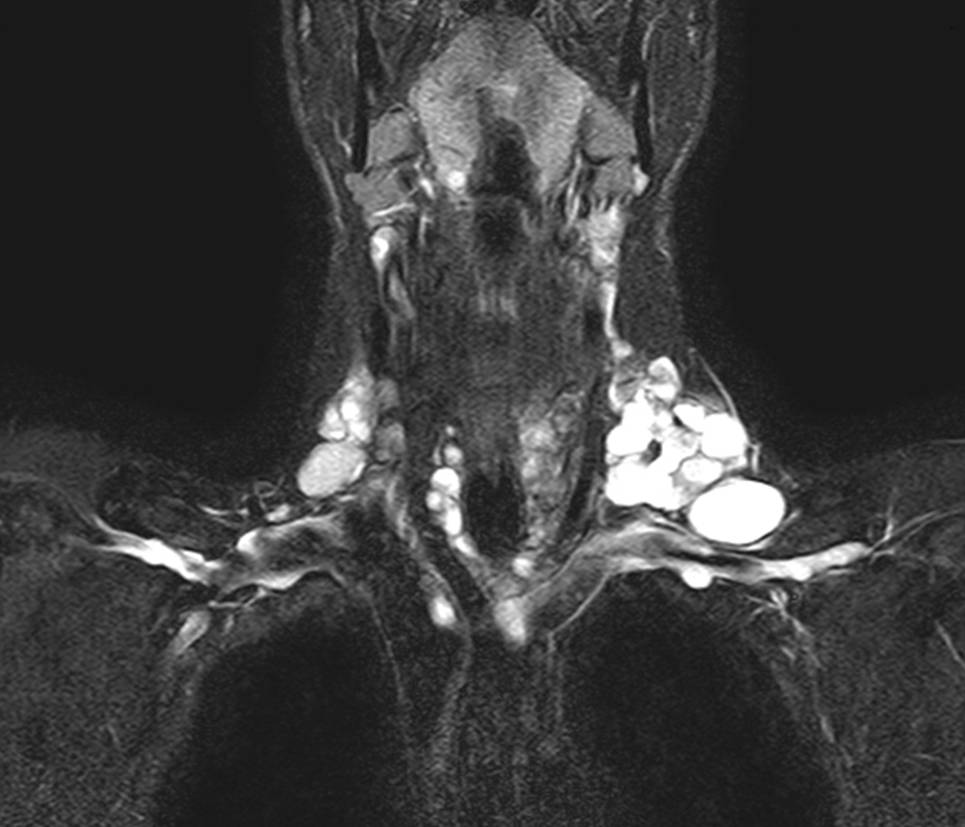

Abb. 3

MRT – die T2 Gewichtung zeigt die 3‑Kompartementmetastasierung eines zystisch-papillären Schilddrüsenkarzinoms

Auch obliegt es letztlich dem Chirurgen, die Ausdehnung einer Struma bereits präoperativ möglichst gut abzuklären. Bei Ausdehnung einer Schilddrüse in den Substernalraum bzw. fehlender sonographischer Abgrenzbarkeit nach caudal ist ergänzend ein Schnittbildverfahren zu wählen, das eine intrathorakale Ausbreitung oder auch isoliert intrathorakale Anteile erfasst und erkennen lässt, ob das vordere oder das hintere Mediastinum betroffen ist. Diese Information ist ganz wesentlich für die Operationsstrategie und die Frage, ob eine Erweiterung des Zugangsweges (z. B. Sternotomie) notwendig sein könnte. Die Szintigraphie kann hier erste Hinweise liefern, wenn das diagnostische Fenster in das obere Mediastinum erweitert wird (Abb. 2a). Als weiterführende Diagnostik ist ein CT ohne Kontrastmittel oft ausreichend (Abb. 2b). Jodhältige Kontrastmittel sind präoperativ grundsätzlich zu vermeiden, da im Falle von differenzierten Karzinomen verbliebene Schilddrüsen- oder Tumorzellen jodgesättigt sind und eine Radiojodtherapie dadurch nur verzögert möglich ist. Ein MRT kann speziell bei zystischen papillären Tumoren das Ausmaß einer Metastasierung in der T2-Gewichtung eindrucksvoll zeigen (Abb. 3) und ist darüber hinaus bei Verdacht einer Infiltration des Aerodigestivtraktes sehr zu empfehlen.